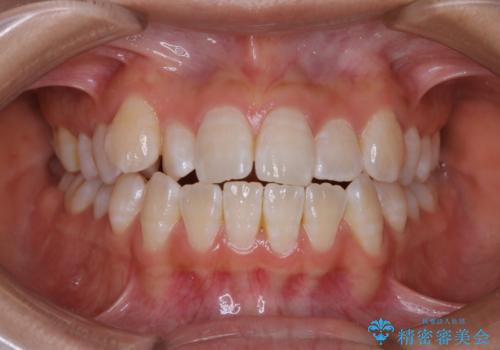

[ 前歯開咬 ] 前歯が噛んでいない マウスピース矯正治療

担当医 大元洋佑

![[ 前歯開咬 ] 前歯が噛んでいない マウスピース矯正治療の症例 治療前](https://seimitsushinbi.jp/wp/wp-content/uploads/2022/11/IMG_4669-500x350.jpg?v=1668218426)